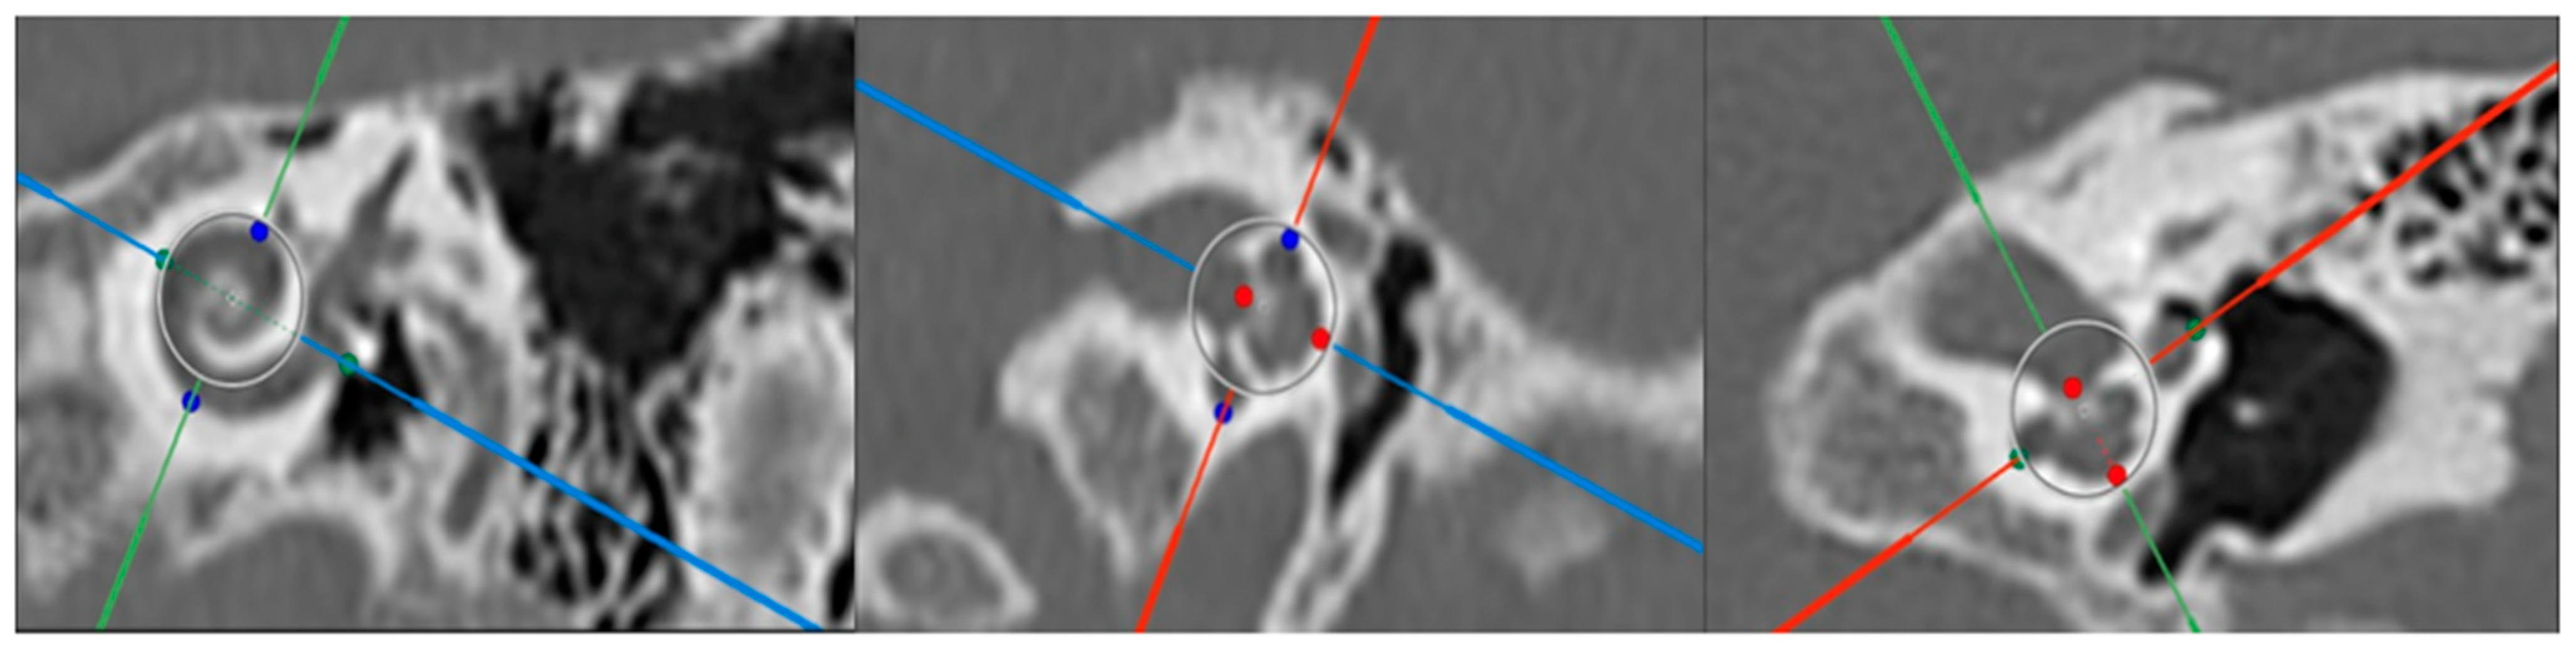

2.2. Cochlear Duct Length Measurements